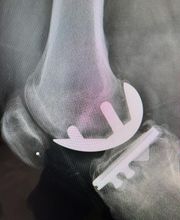

Il Dottor Pera Antonio esercita la professione medica presso il proprio studio ubicato a La Spezia, dove riceve su appuntamento. Pera dr. Antonio è medico chirurgo specializzato in Ortopedia e Traumatologia, anche infantile. Pera dr. Antonio è attualmente iscritto alla S.I.O.T.(Società Italiana di ortopedia e traumatologia); S.I.A.(Società italiana di artroscopia) di cui risulta essere socio onorario; A.L.A.(Associazione ligure di artroscopia); S.I.T.R.A.S.(Società italiana di traumatologia dello sport); S.P.L.L.O.T.(Società piemontese ligure e lombarda di ortopedia e traumatologia); Club di Chirurgia del ginocchio. Dal Gennaio 2012 Pera dr. Antonio svolge il ruolo di Delegato Regionale S.I.A.(Società Italiana di Artroscopia) per la Liguria. Riceve solo su appuntamento.